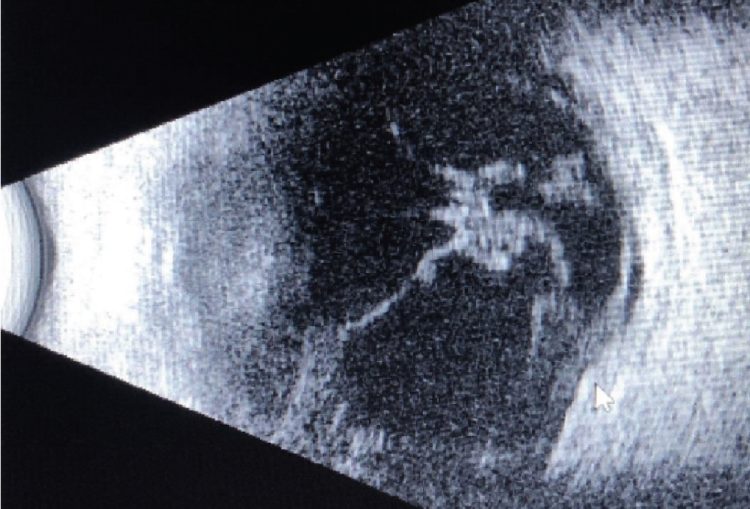

En el examen clínico, se observó un gran defecto epitelial que medía 10 mm x 6 mm, con un área de necrosis coagulativa central y extensión a la esclerótica superior. El A/C era profundo y estaba formado por un denso hipopión. La ecografía B-scan realizada mostró vitritis, lo que era preocupante para endoftalmitis.

Caso 1. Ecografía B-scan tomada en el examen preoperatorio. Aún se observan restos vítreos, desde la presentación inicial.